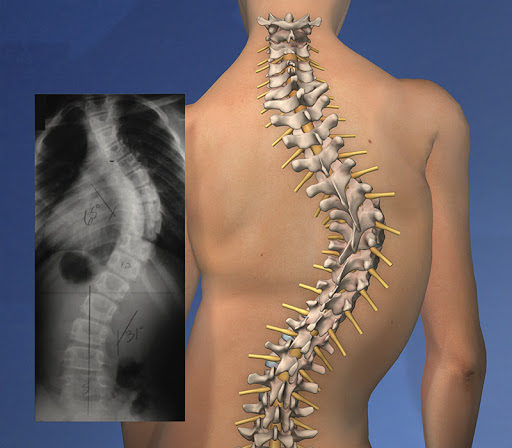

ستون فقرات هر فرد انحناهای طبیعی دارد. این انحناها باعث گرد شدن شانه ها و فرو رفتن کمر به طرف داخل می شوند. برخی افراد دارای انحنا در طرفین ستون فقرات خود هستند که با راست نشستن و صاف ایستادن به راحتی اصلاح نمی شود. این انحنای جانبی ستون فقرات اسکولیوز نامیده می شود. اگر کسی که اسکولیوز دارد از ستون فقرات خود عکس رادیوگرافی بگیرد، ستون فقراتش به جای اینکه به صورت یک خط صاف دیده شود به شکل یا دیده می شود. این انحنا باعث کج به نظر رسیدن شانه ها و کمر شخص می گردد. در بعضی موارد ممکن است چند تا از مهره ها در اسکولیوز مقداری چرخیده باشند که باعث برجسته شدن بیشتر یک کتف به طرف مقابل می شود. اسکولیوز یک تعریف است نه یک تشخیص و در بیشتر از 80 درصد از موارد، دلیل به خصوصی برای این مشکل پیدا نمی شود. این نوع از اسکولیوزها، ایدیوپاتیک به معنی “ناشناخته” نامیده می شوند. این نوع از اسکولیوز در بین دخترانی که هنوز به بلوغ نرسیده اند رخ می دهد. عواملی که باعث کج شدن ستون فقرات می شوند عبارتند از: عوامل غیر طبیعی مادرزادی، عوامل ارثی، عوامل عصبی و … اما از طریق عواملی مانند وضعیت بد خوابیدن یا حالت بخصوص ایستادن، فعالیت های ورزشی و یا اختلاف طول اندام های تحتانی ایجاد نمی شود.

میزان انحراف ستون فقرات در اسکولیوز متوسط 20 تا 40 درجه است. در این مرحله استفاده از بریس به نوجوانانی که به این مشکل دچار شده اند توصیه می گردد. چرخش ستون فقرات فرد در اسکولیوز متوسط با توجه به اندام فرد مشخص می شود. در هنگام خم شدن، دنده ها و کتف رو به جلو هستند برای مثال در تست آدامز از پشت مشخص است و شانه ها در یک راستا قرار نمی گیرند.

در اسکولیوز شدید زاویه Cobb در نوجوانان 40 تا 45 درجه می باشد و در بزرگسالان این زاویه 50 تا 55 درجه می باشد. چنانچه این اسکولیوز بسیار شدید باشد مشکلات جدی ریوی و قلبی بروز پیدا می کند. پس در درمان حالت شدید این مشکل نباید سهل انگاری شود. در این شرایط بریس برای جلوگیری از شدید شدن وضعیت اسکولیوز تجویز می شود اما نمی تواند آن را درمان کند و برای درمان آن باید جراحی انجام شود. جراحی به این منظور انجام می شود که اثرات اسکولیوز کاهش یابد یا در جهت معکوس کردن تغییرات باشد. اما باید گفت که جراحی همیشه در پیشگیری از پیشرفت این عارضه موفق نیست. به همین دلیل است که از دید متخصصان تشخیص و درمان زودهنگام بسیار مهم است.